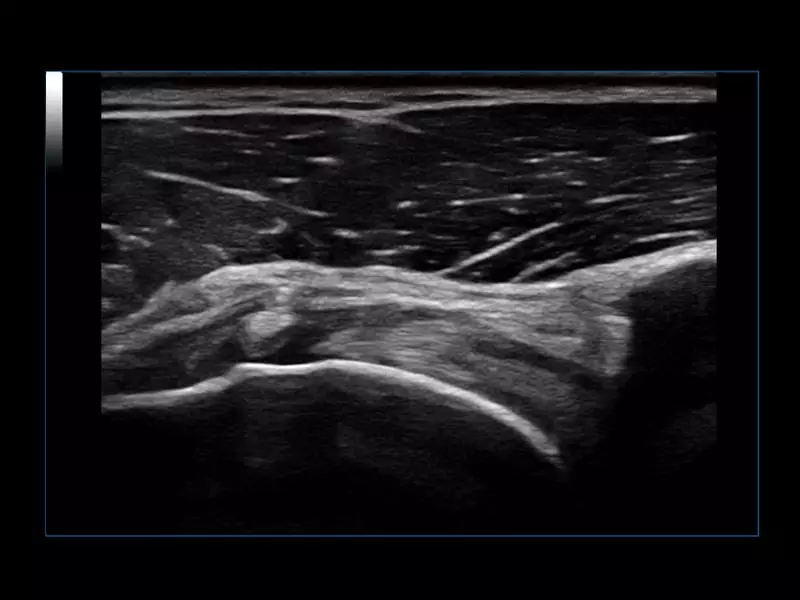

MyLab™X1 - Tendon

MyLab™X1 - Tendon